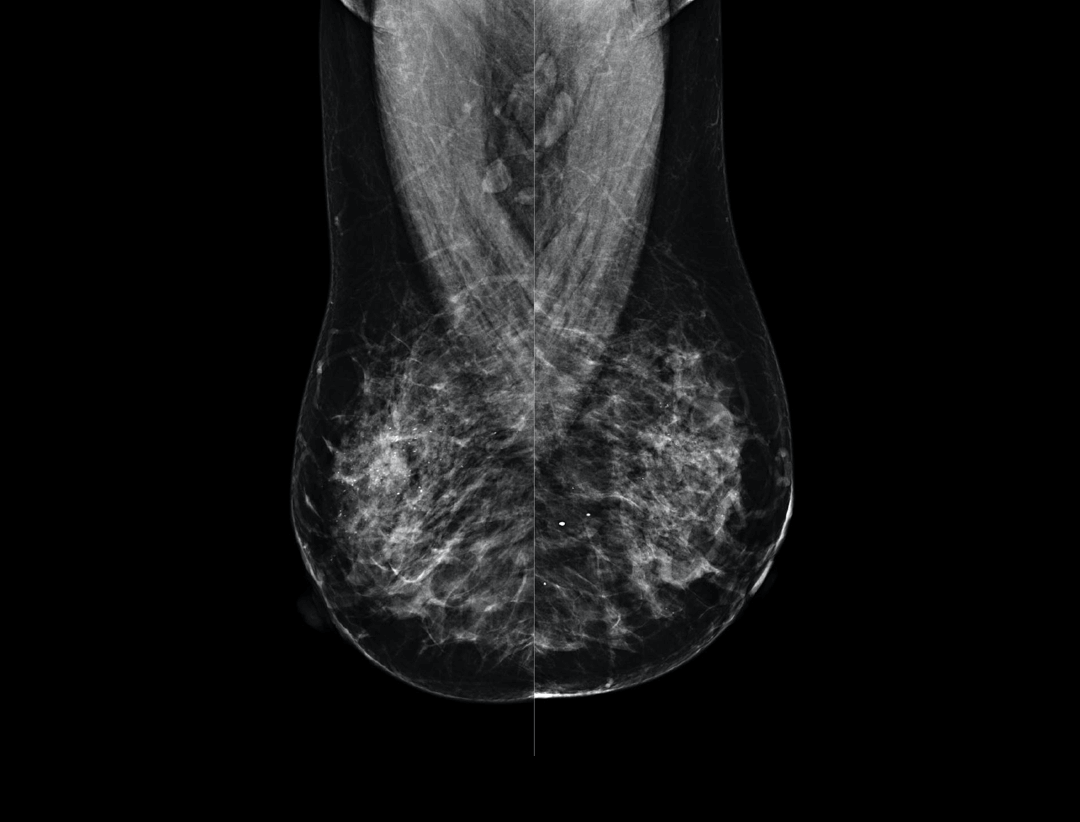

High Resolution Low Dose Imaging

Large coverage amorphous-silicon (a-Si) flat panel detector featuring an optimized active matrix array provides high spatial resolution and high image acquisition speed at a lower dose.

High performance tungsten target X-ray tube offers high resolution image for both dense and fatty breast densities.

Intelligntly detects breast density and thickness, then auto selects the appropriate filter combination.